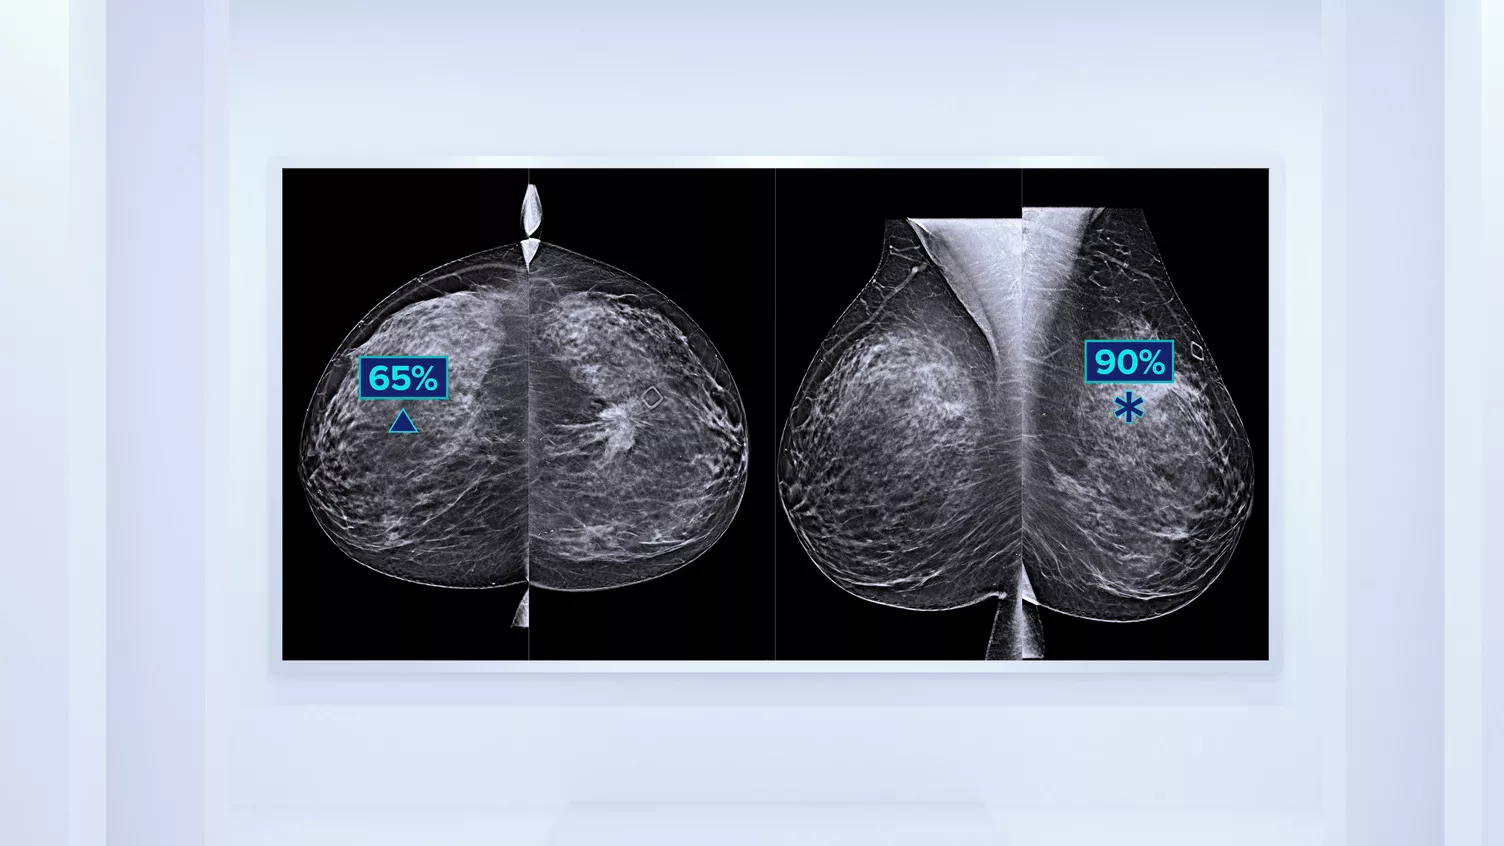

In addition to volume, pattern and texture of fibroglandular tissue may play just as an important role in mammographic cancer risk prediction.3-5 By analysing and categorising breast texture and pattern, our technology can deliver the accurate information you need to achieve more consistent and reliable scoring and confidently design patient-specific screening.

Objective machine learning algorithm that assigns breast density category based on analysis of breast tissue texture and patterns.

Displays density on the acquisition workstation to facilitate patient management protocols for potential supplemental imaging.

Quantra software’s unbiased algorithm analyse both 2D and tomosynthesis images to support your analysis by:

• Overcoming subjectivity in visual assessment, providing more consistent, and more reliable scoring.*

• Facilitating patient management protocols for supplemental imaging.